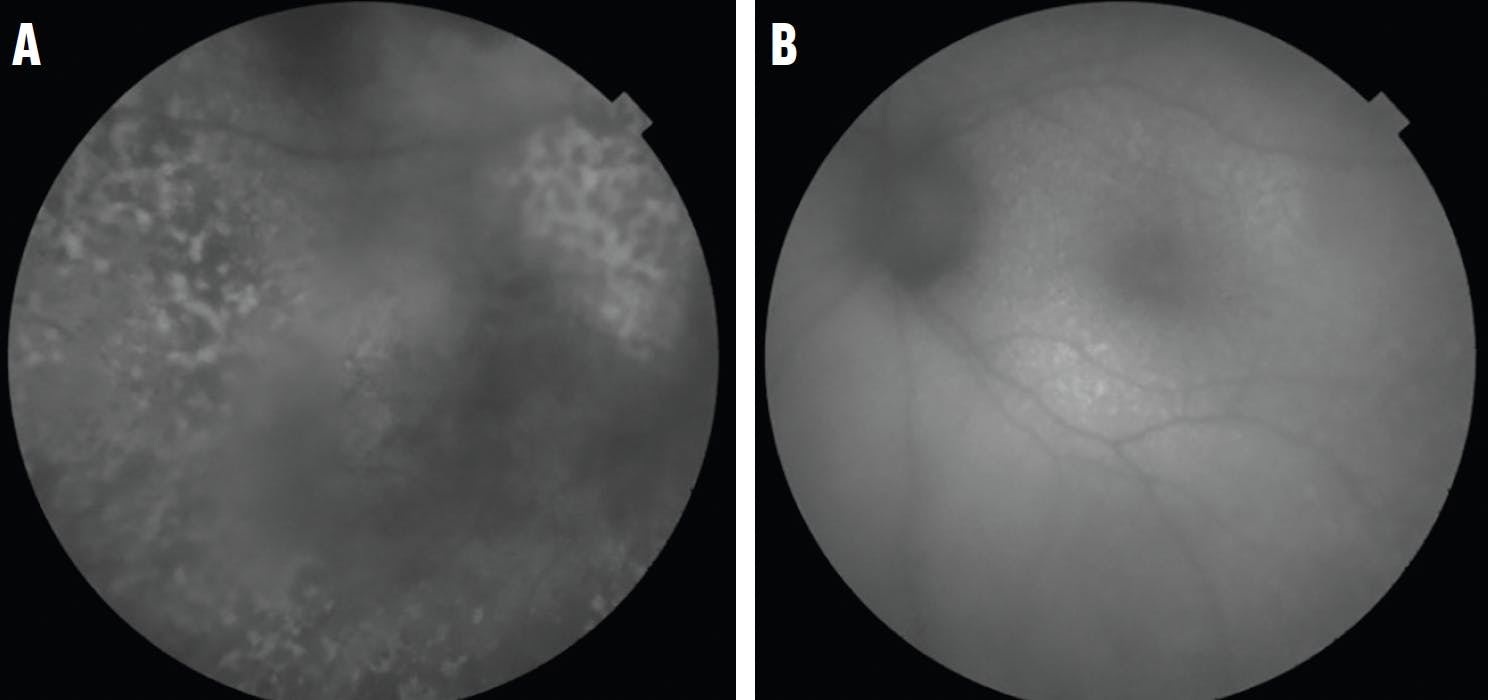

• Vitreous and Posterior Segment Findings: Massive cellular infiltration (vitreous sheets or clumps) with the absence of macular edema, snowbanking, or vitreous hemorrhage may be present. There are usually multifocal creamy/white lesions in the outer retina (Figure 1) with or without a leopard-spot appearance, and retinal pigment epithelial (RPE) atrophy or fibrosis.

<p>Figure 1. Fundus images of the right eye of a 55-year-old man on presentation showed multifocal creamy/white lesions in the outer retina with leopard-spot and RPE atrophy typical of intraocular lymphoma. This patient underwent vitrectomy, which confirmed the diagnosis, and he developed brain lymphoma 14 months later.</p>

Figure 1. Fundus images of the right eye of a 55-year-old man on presentation showed multifocal creamy/white lesions in the outer retina with leopard-spot and RPE atrophy typical of intraocular lymphoma. This patient underwent vitrectomy, which confirmed the diagnosis, and he developed brain lymphoma 14 months later.